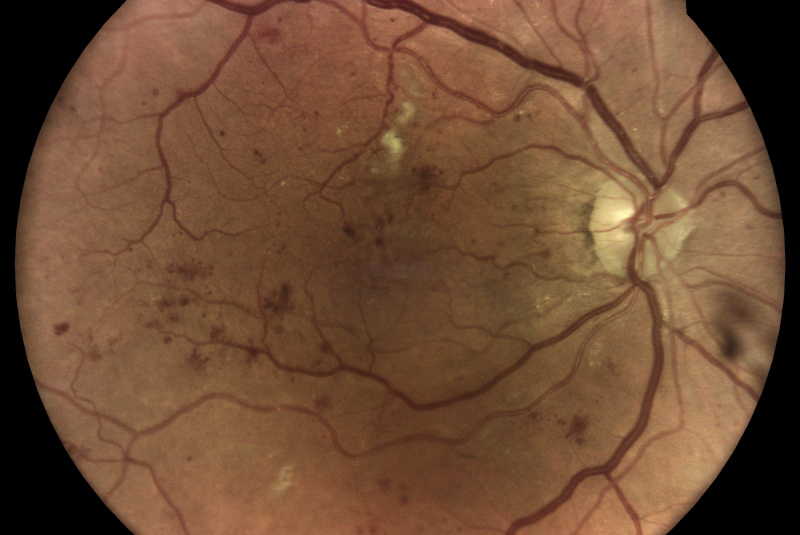

Oproti běžným fundus kamerám je zde využita patentovaná technologie iCare DRS Plus Confocal Technology. Snížená intenzita záblesku má šetrnější účinek na zornici. Prostřednictvím tohoto nemydriatického zařízení je možnost vidět jemné struktury sítnice a cévního systému i skrze velikost zorničky od 2,5 mm.

Fundus kamera iCare DRSplus pořídí celkem 4 vysoce kvalitní snímky (dva z pravého a dva z levého oka), které se automaticky ukládají na cloud a posílají se na zpracování AI - umělé inteligenci. Report je dostupný ihned a ten je možno konzultovat s pacientem během téže návštěvy u lékaře.

- infračervené mapy zvýrazňující světlé a červené léze/poškození